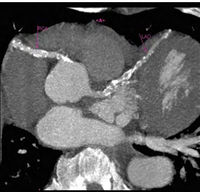

Несколько исследований показали, что спортсмены, использующие ААС, имеют сокращенный диастолический объем, более толстую заднюю стенку и межжелудочковую перегородку, а также большую массу левого желудочка, в отличие от спортсменов, не использующих ААС. Сердечные мышечные клетки имеют рецепторы чувствительные к андрогенам, и ААС способны вызывать их гипертрофию, действуя непосредственно на клетки. Проблема в том, что гипертрофия левого желудочка может сохраняться после прекращение приема ААС.

Эхокардиографическое исследование 47 лиц, 28 из которых регулярно использовали ААС, показало более низкую систолическую функцию в группе пользователей ААС, чем у не использующих. Кроме того, показало фракцию выброса 58% против 63% - соответственно. Также, при помощи дооплерографии, были выявлены признаки уменьшения диастолической функции (сердце было слабее и жестче).

Также было установлено, что растяжимость аорты уменьшается у спортсменов, которые используют ААС. Жесткость аорты (ЖА) за счет увеличения нагрузки на желудочки предрасполагает к развитию гипертрофии левого желудочка, развивает дисфункцию левого желудочка, сердечную недостаточность, а также нарушает баланс потребляемого и получаемого кислорода. Также ЖА приводит к снижению давления в аорте во время диастолы, что уменьшает давление коронарной перфузии и способствует ишемии миокарда, даже в отсутствие атеросклеротического сужения коронарной артерии.